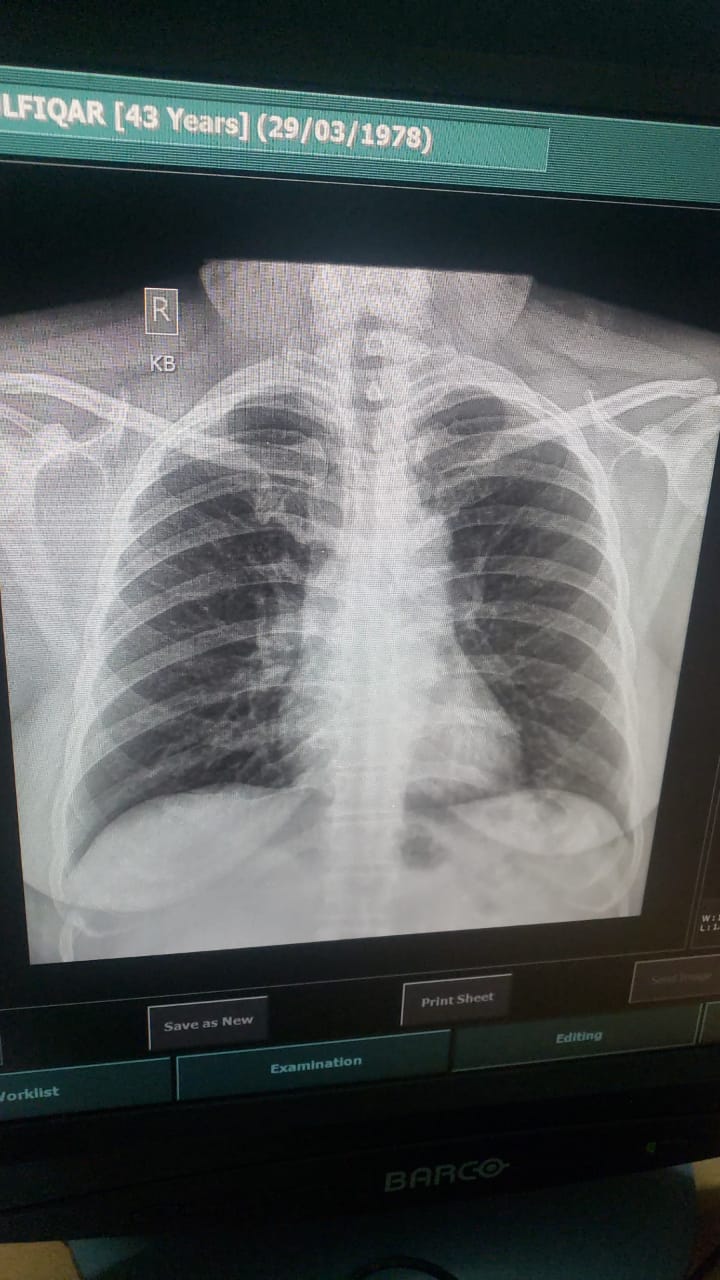

Asking for Mother, Female, 43 years old, Karachi

My mom is 43 years old and she’s had Covid since a week. Her symptoms now are much better AH but she still has troubled breathing and cough with sputum . Doctor suggested to get a chest X-ray so here’s her chest X-ray. Can you please tell is there any problem?

x ray is normal but can get an online appointment for a detailed discussion of symptoms

Alhamdolillah her xray ok plz share her oxvgen saturation and Cbc